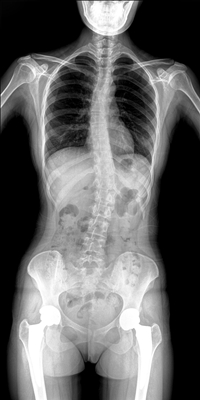

臨床需要對(duì)患者的脊柱情況有全面了解,故而術(shù)前術(shù)后均需要均需要借助DR拍攝X光片便于分析病情、明確診斷及術(shù)后觀察治療效果。大視野動(dòng)態(tài)DR可以對(duì)患者的脊柱進(jìn)行長(zhǎng)尺寸攝影,一次拍攝就能獲取完整的脊柱全景圖像。診斷醫(yī)生通過(guò)拍攝后的影像測(cè)量全脊柱的生物角度、Cobb角等,為脊柱側(cè)彎的畸形矯正患者術(shù)前術(shù)后的檢查提供重要的診斷依據(jù)。

通過(guò)大視野動(dòng)態(tài)DR進(jìn)行全脊柱攝片,其得到的影像密度均勻、清晰、接緣處過(guò)渡自然。且操作更加便捷,不需要二次攝片然后進(jìn)行圖像拼接,拍攝時(shí)間短,效率高。在減少輻射劑量的同時(shí)也能為臨床醫(yī)生帶來(lái)更精確的診斷信息。非拼接影像可保證雙腿測(cè)量(如力線(xiàn))數(shù)據(jù)的準(zhǔn)確性,有效避免攝影信息的丟失。給手術(shù)醫(yī)生提供準(zhǔn)確的術(shù)前診斷數(shù)據(jù),提高手術(shù)成功率。

綜上所述,大視野動(dòng)態(tài)DR進(jìn)行全脊柱成像能夠清晰的呈現(xiàn)骨關(guān)節(jié)結(jié)構(gòu),可以在全景脊柱圖像基礎(chǔ)上對(duì)角度值進(jìn)行測(cè)量,能夠很好的反映骨骼的真實(shí)比例與長(zhǎng)度,為臨床診斷和治療提供了更精確的數(shù)據(jù),有著重要臨床應(yīng)用價(jià)值。